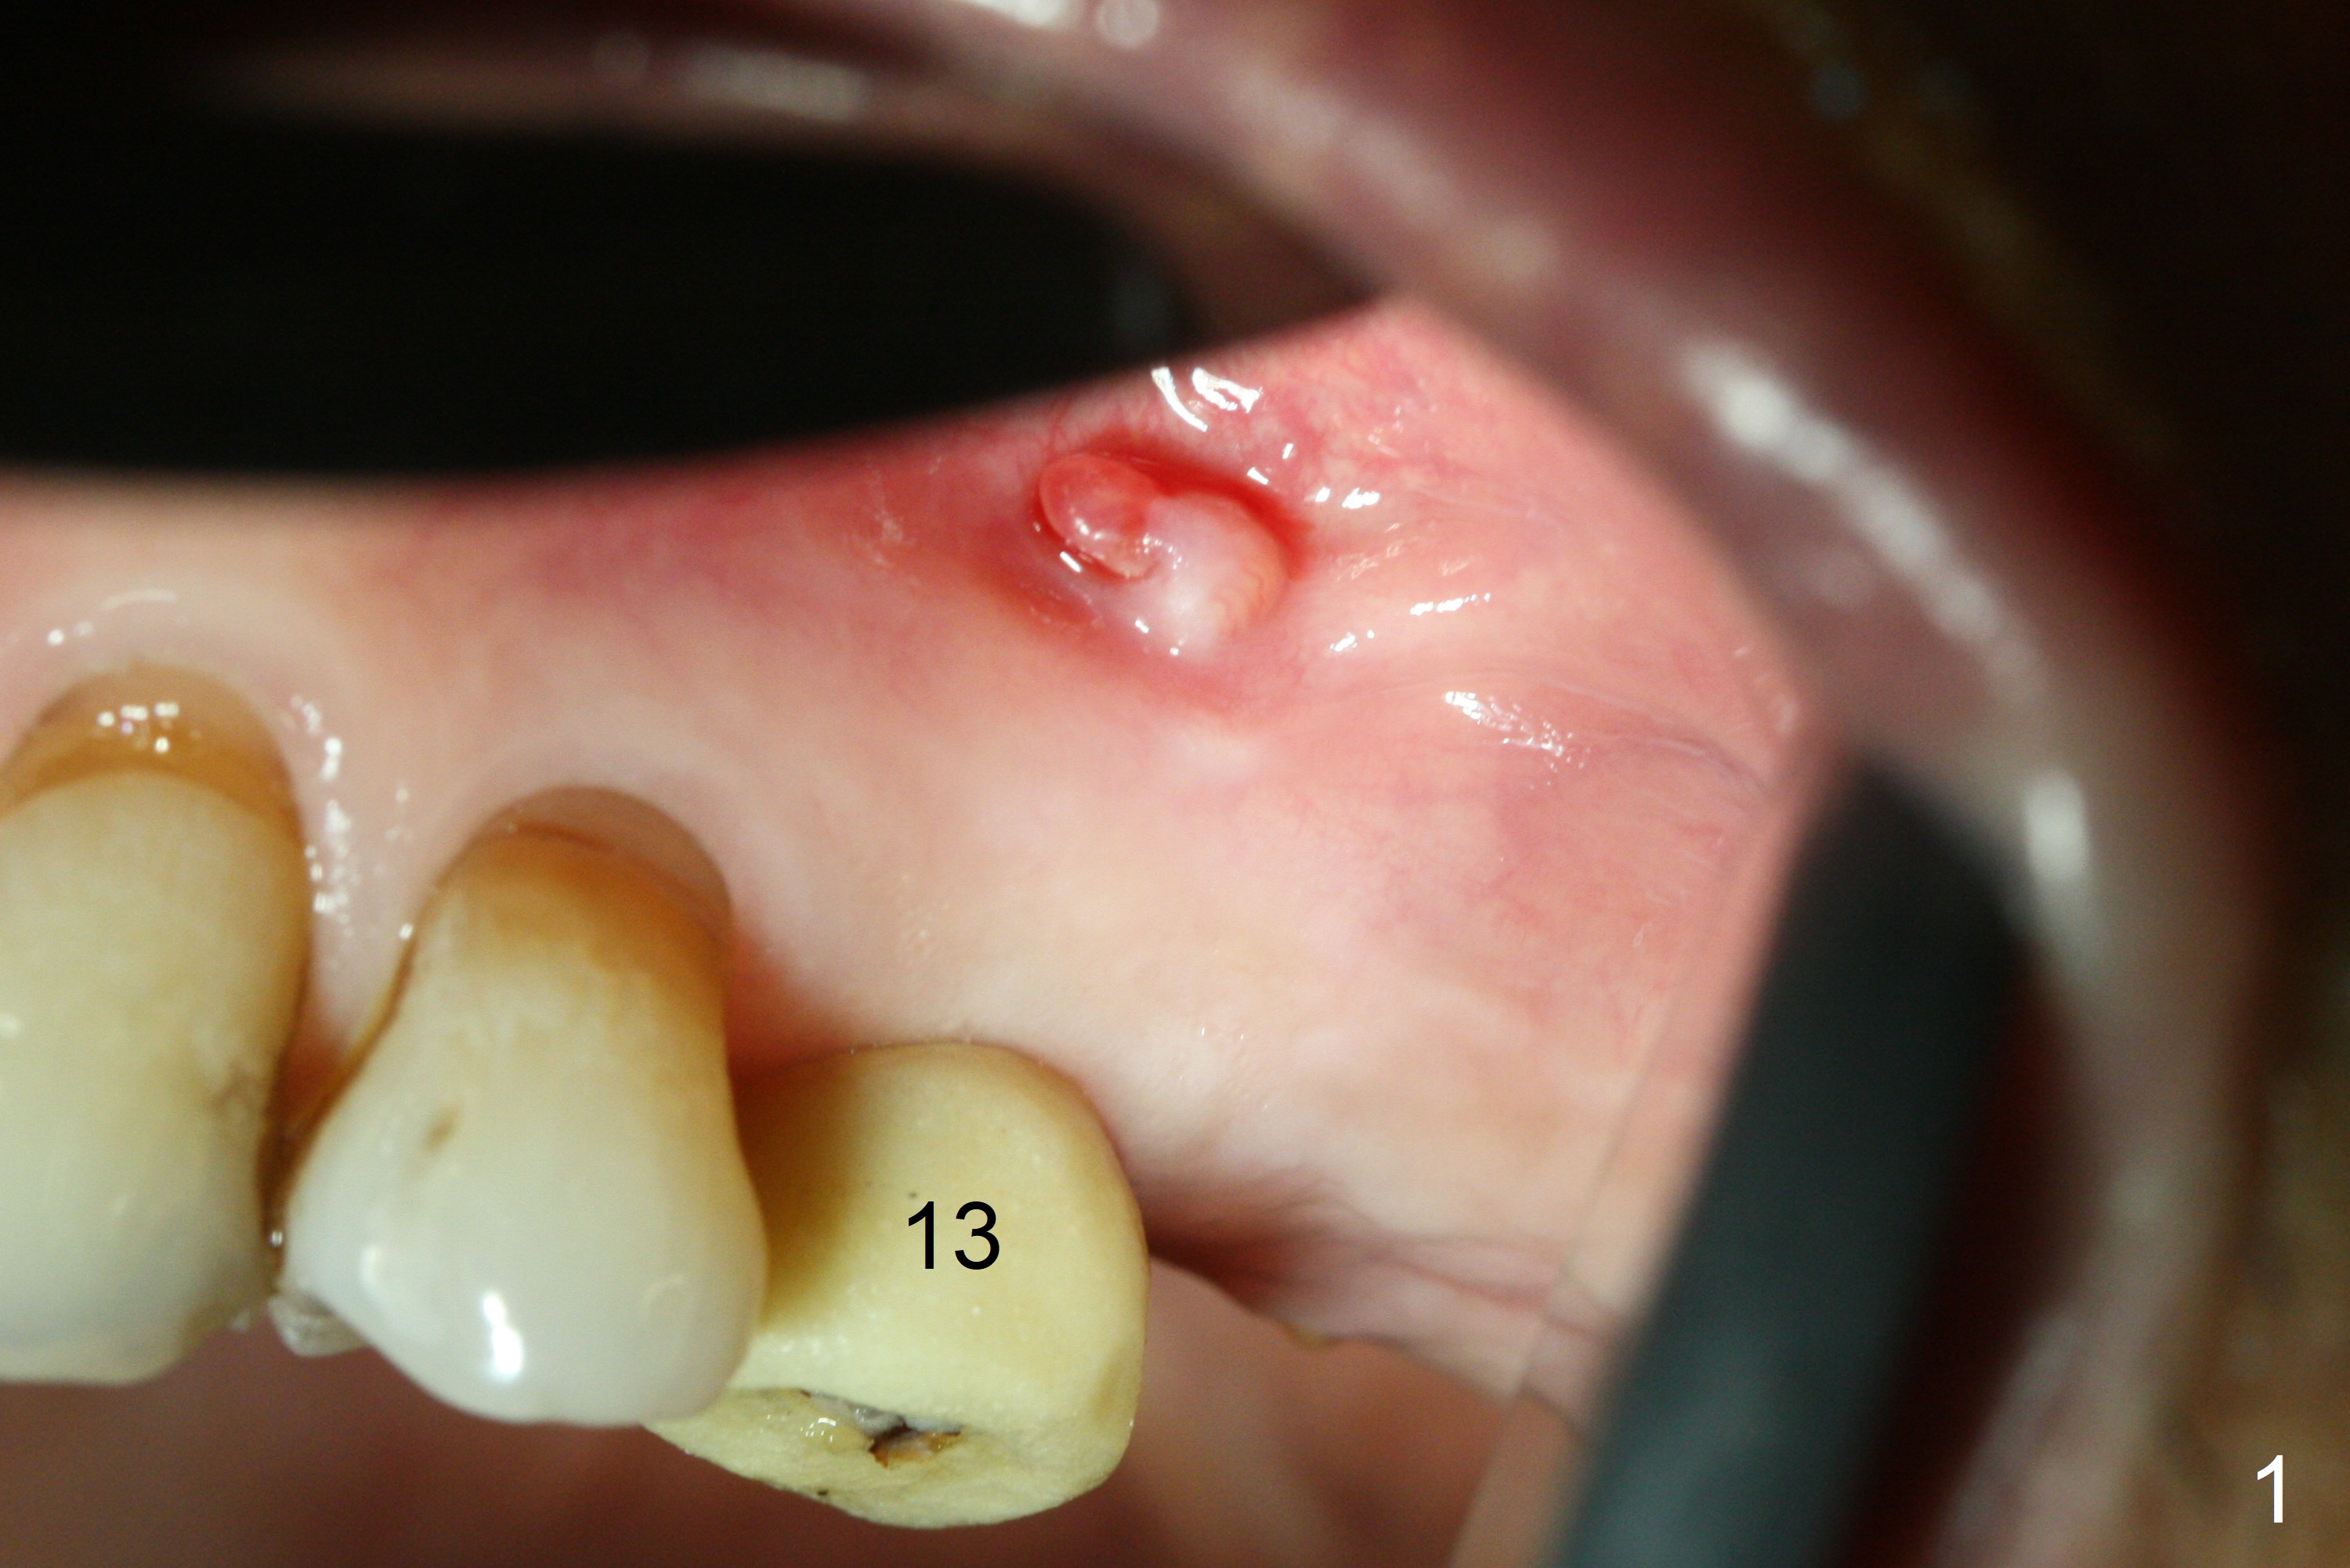

A fistula is found apical to #13 immediate implant 9 months postop (Fig.1). It is curetted without bony defect. Osteotomy at #15 is accomplished with traditional tapered osteotomes from 2 to 5 mm for 11 mm deep. Although the patient is a little uncomfortable with tapping (as compared to Magic Expanders), a 4.5x11 mm dummy implant is placed 2 mm subgingival with primary stability (Fig.2). Finally a 5x11 mm IBS implant (2 mm longer than the previous one) is placed with insertion torque > 50 Ncm; a 6x2 mm healing abutment is placed (Fig.3,4). The advantages of the flapless surgery (because of the wide ridge) include no allograft or suture. The fistula apical to #13 implant disappears 3 days postop (Fig.5), while the gingiva attaches to the healing abutment at #15 (Fig.6).